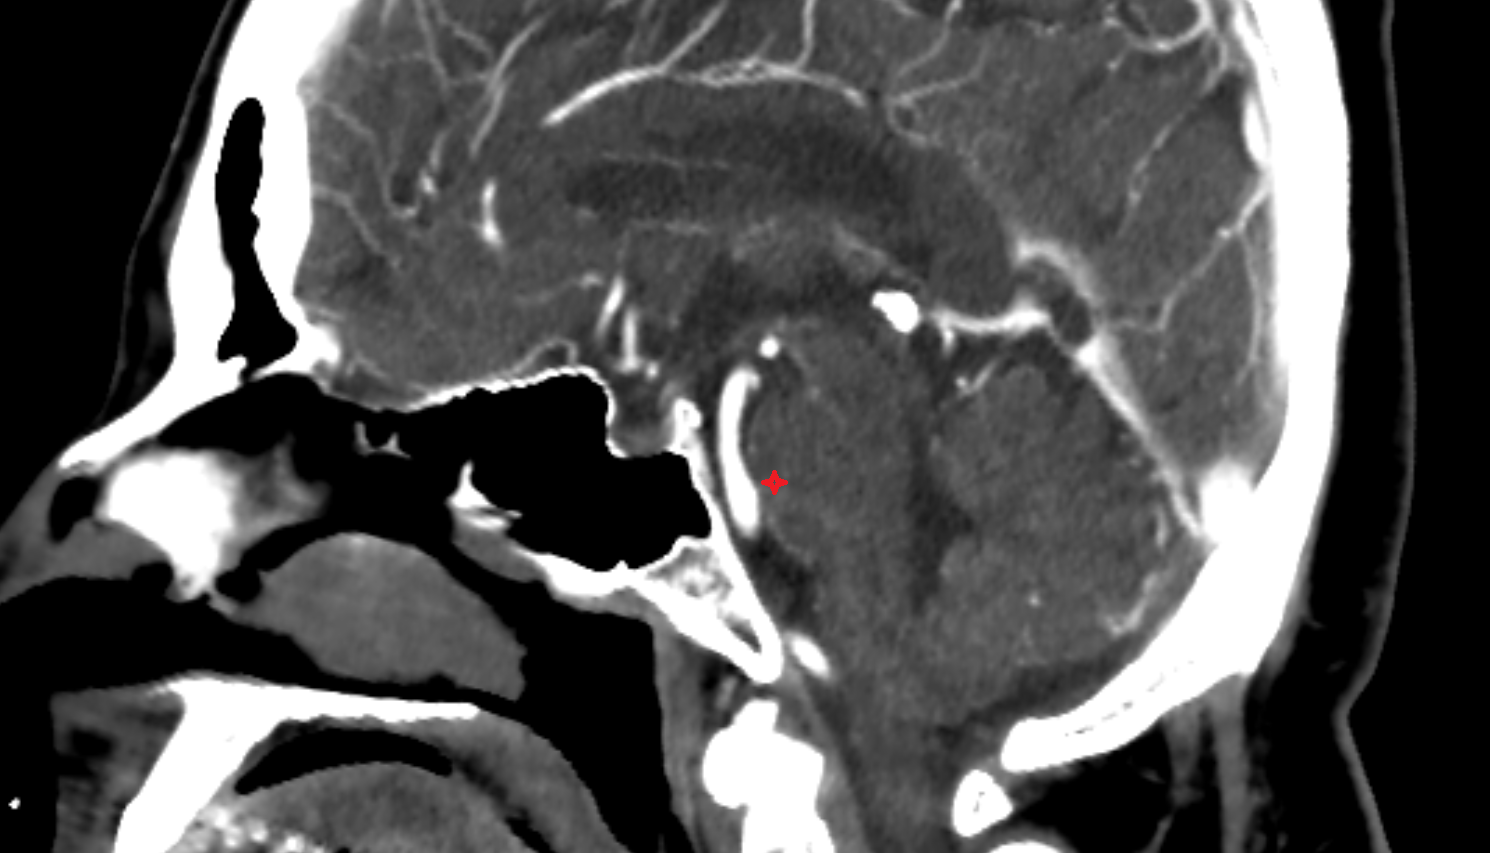

- Carotid bifurcation

- Internal carotid artery (cavernous part)

- Internal carotid artery (cervical part)

- Internal carotid artery (petrous part)

- Clivus

- Sella turcica